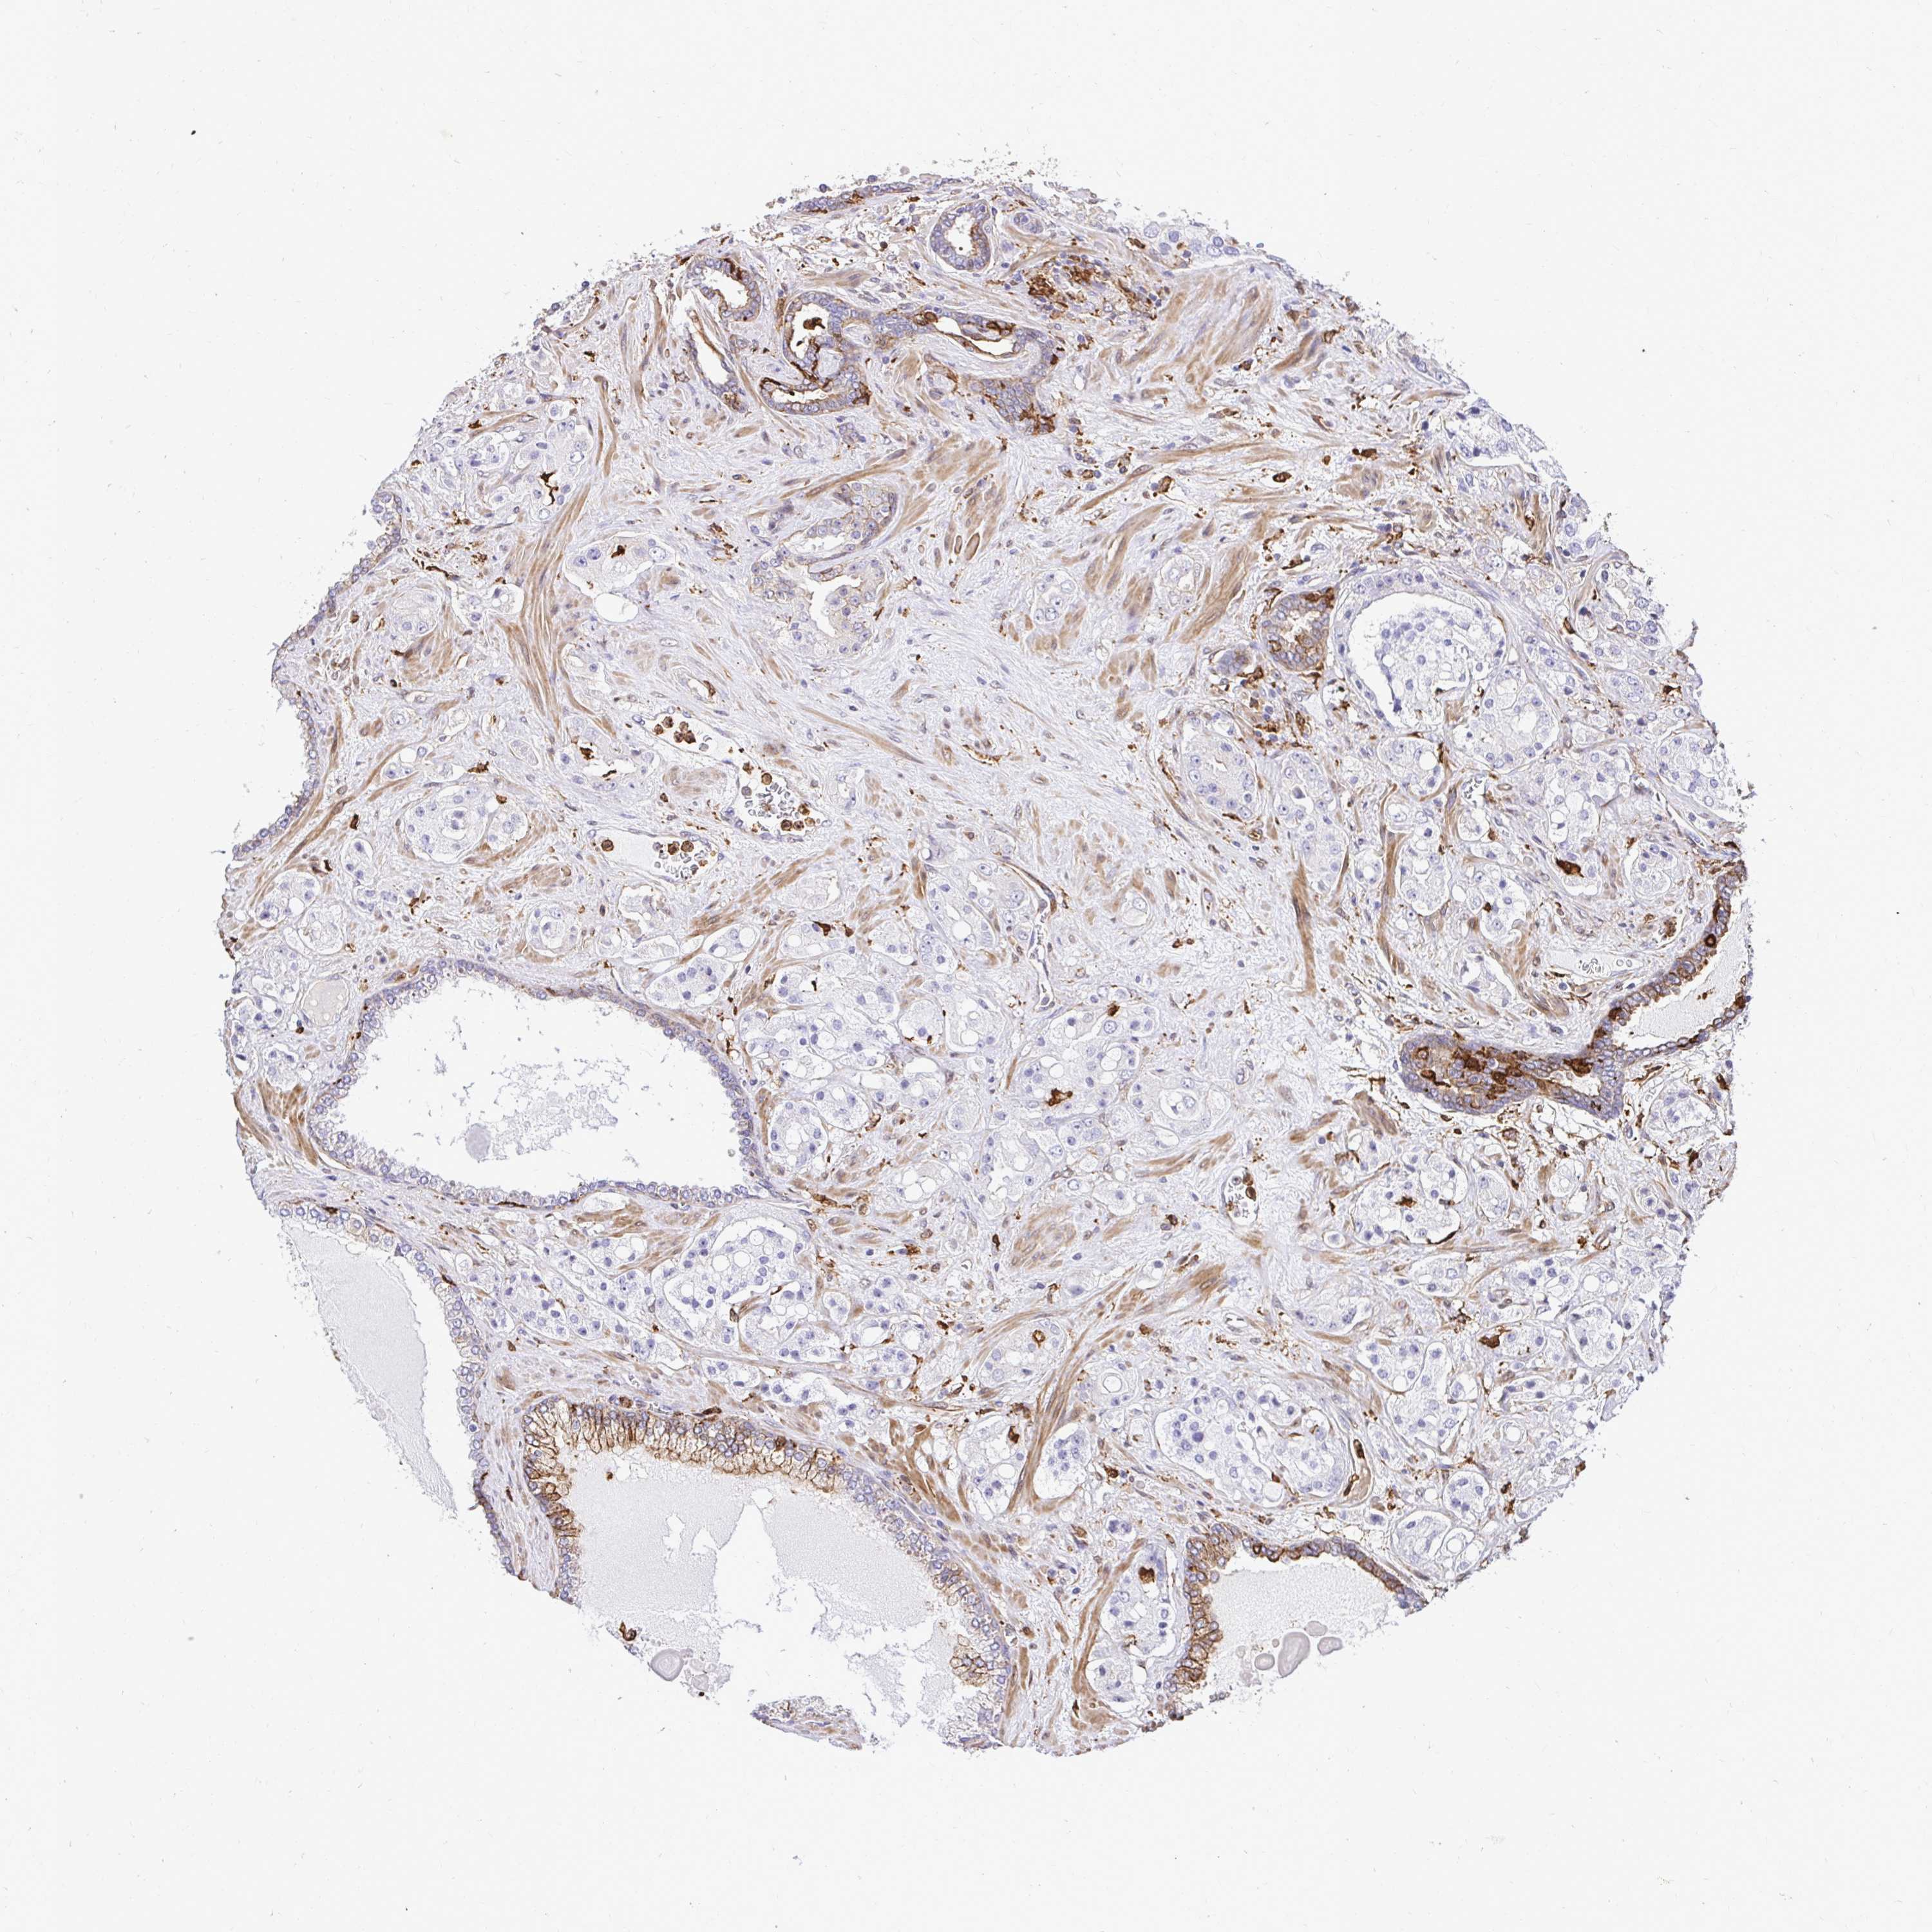

PROSTATE CANCER - Protein expressioni

A mouse-over function shows sample information and annotation data. Click on an image to view it in a full screen mode. Samples can be filtered based on level of antibody staining by selecting one or several of the following categories: high, medium, low and not detected. The assay and annotation is described here.

Antibody stainingi

Antibody staining in the annotated cell types in the current human tissue is reported as not detected, low, medium, or high, based on conventional immunohistochemistry profiling in selected tissues. This score is based on the combination of the staining intensity and fraction of stained cells.

Each image is clickable and will lead to virtual microscopy that enables deeper exploration of all samples and also displays staining intensity scores, fraction scores and subcellular localization as well as patient and tissue information for each sample.

Antibody HPA054026

Antibody CAB010823

Antibody CAB016728

Antibody CAB036009

Staining

High

Medium

Low

Not detected

Intensity

Strong

Moderate

Weak

Negative

Quantity

>75%

75%-25%

<25%

None

Location

Nuclear

Cytoplasmic/membranous

Cytoplasmic/membranous,nuclear

Adenocarcinoma, High grade

Adenocarcinoma, Low grade